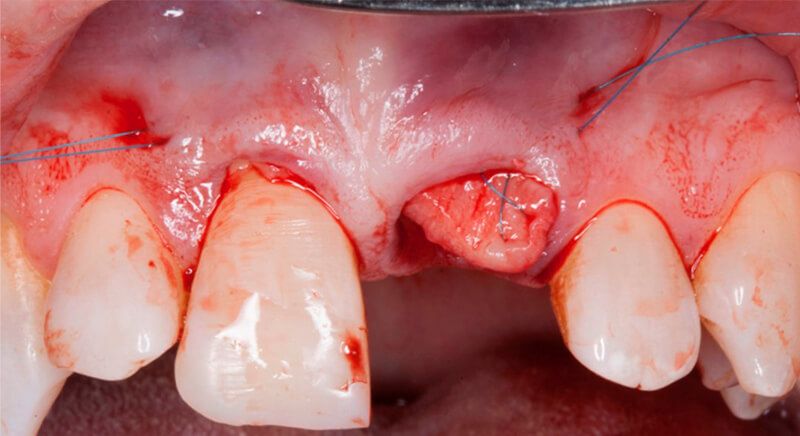

The socket was filled with a xenograft after the extraction and a graft of connective tissue was placed in the vestibular area of the two upper central incisors.

The tissue with epithelium was taken from the palate and de-epithelialized outside of the mouth. This obtains a lamina propria graft with better density and quality than if it were obtained with a single incision to the palate.

Once the hard and soft tissues had healed, 6 months after the surgery, a good volume remained in the vestibular area. It was then that we could consider an implant, using guided surgery to ensure it was placed in the correct three-dimensional position.